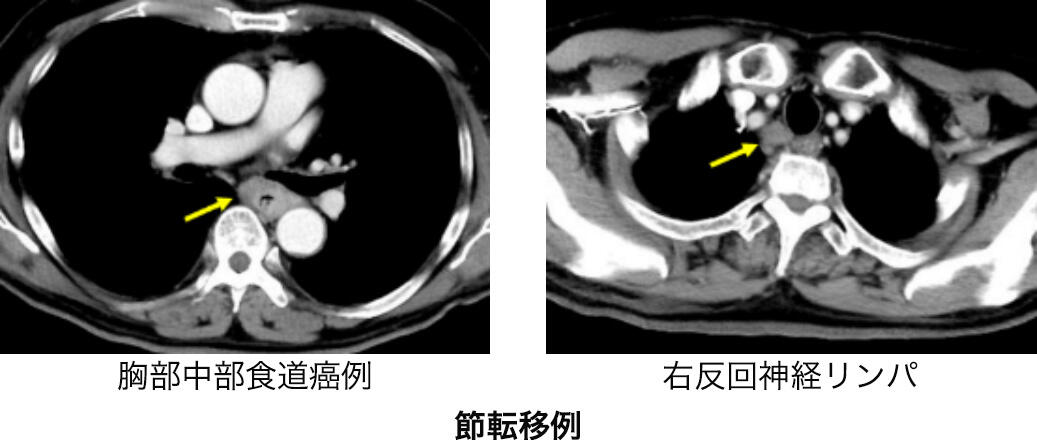

CT検査

CT(コンピューター断層撮影)で頸部から腹部までの撮影を行います。造影剤を併用することで血流のコントラストが鮮明となり診断能が高まります。食道癌の壁深達度がどうであるか、他臓器(気管、大動脈など)への浸潤はないか、食道周囲や遠くのリンパ節に転移がないか、肺や肝臓など他臓器に転移がないか、そして手術を検討するに解剖学的特徴について調べます。